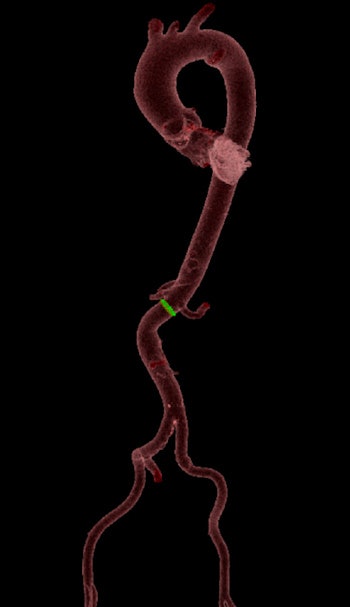

The group conducted a retrospective study to evaluate the effectiveness of a 256-slice CT scanner prior to mitral and aortic valve surgery in the evaluation of the aortoiliac femoral axis and coronary arteries. Their sample consisted of the first 64 consecutive patients (74.2 ± 17.2 years; 33 women, 31 men) scheduled for mitral. The patients underwent CT with a 256-slice-CT system (Revolution CT, GE Healthcare), the exclusion criteria being contraindications to contrast agents and impaired renal function.

The researchers conducted axial prospective assessment (cardiac cycle phases 40% to 80%). ECG-gated scanning was utilized to examine the thorax, and spiral non-ECG-gated scanning of the abdomen immediately followed. The contrast flow was 5 mL per second, followed by 50 mL physiological solution and use of iterative reconstruction (adaptive statistical iterative reconstruction, ASIR-V at 50%). Two experienced radiologists and one resident radiologist performed the analysis.

The evaluation of the peripheral access vessels and dimensions of the ascending aorta, aortic root, and aortic annulus (when requested) were performed in all patients. The mean cardiac frequency was 74.18 ± 12.32 bpm, and the presence of atrial fibrillation in six patients did not affect the diagnostic performance, Fiore and colleagues noted.

The authors compared the coronary arteries in a CT angiography examination and an invasive coronary angiography exam by studying four vessels: the left coronary artery common trunk, left coronary artery anterior descending branch, circumflex artery, and right coronary artery. Ten vessels were not assessable in the CT angiography examination because of artifacts due to the presence of widespread calcifications or patient movement artifacts.